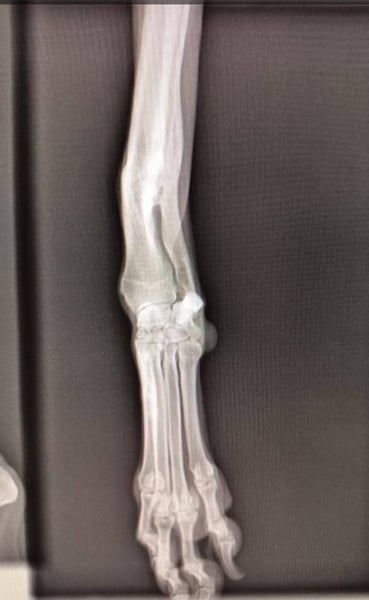

Wahrscheinlich wurde sie aufgrund eines verheilten Bruchs im Vorderbein ausgesetzt. Diese leichte Verletzung hindert sie nicht daran, ein normales Leben zu führen und eine Operation ist nicht notwendig.